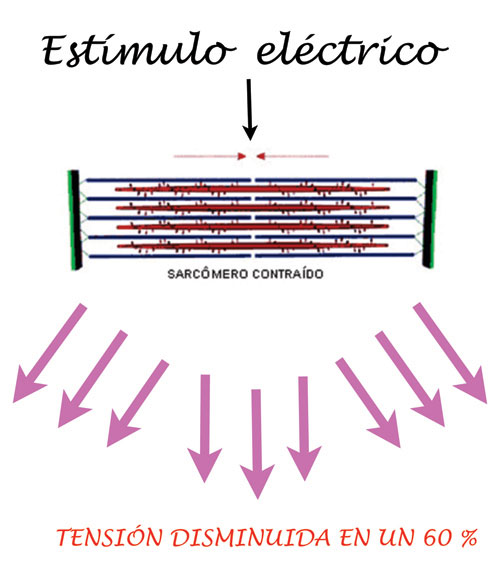

Sabemos por fisiología , que cuando un estímulo eléctrico es aplicado a un músculo acortado en su longitud es decir, con sus sarcómeros contraídos, la capacidad de contracción ante el estímulo se encuentra disminuida en un 60%.

DIBUJO I